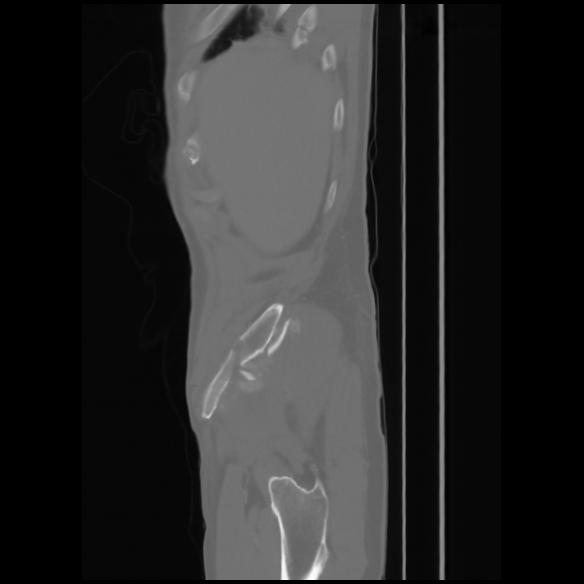

7 CUERPO,CE,Sagittal,3.000,CUERPO,Sagittal,